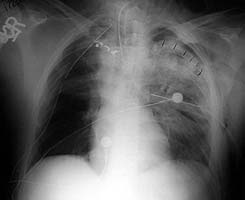

Enclosed are three figures--the CXR of a male with a left to right transmediastinal GSW of upper chest--no hard signs of vascular injury except for about 1000 cc blood out of left chest tube which eventually stopped without surgery. Next is angio #1 showing intimal defect in innominate artery right at the takeoff of the Rt subclavian and carotids. F/U angio one week later--no surgery--documents complete resolution of the intimal injury. There were no symptoms, including the blood from the left chest, attributable to this injury, thus fulfilling the criteria for observation.

Initial CXR